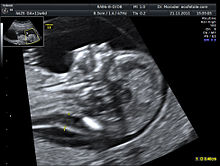

Ultrasound

Ultrasound imaging can be used to screen for Down syndrome. Increased fetal nuchal translucency (NT) is an indicator of increased risk of Down syndrome. A 2003 systematic review of 30 studies of NT in Down syndrome found an average sensitivity of 75-80% with a false positive rate of 5.8-6% (95% confidence intervals). Therefore, while the false positive rate is too high for NT to be used alone as a screening test, it is useful as part of a combined test. Ultrasound measurement of NT is usually performed between 11 and 14 weeks gestation.

Other ultrasound findings have been associated with Down syndrome. Absence of the fetal nasal bone has been associated with Down syndrome. A 2001 observational study suggested that there is an increased rate of absence of nasal bone in fetuses with Down syndrome. However, it is unclear how useful this would be as a screening test as the reproducibility and consistency of the procedure has not been demonstrated.